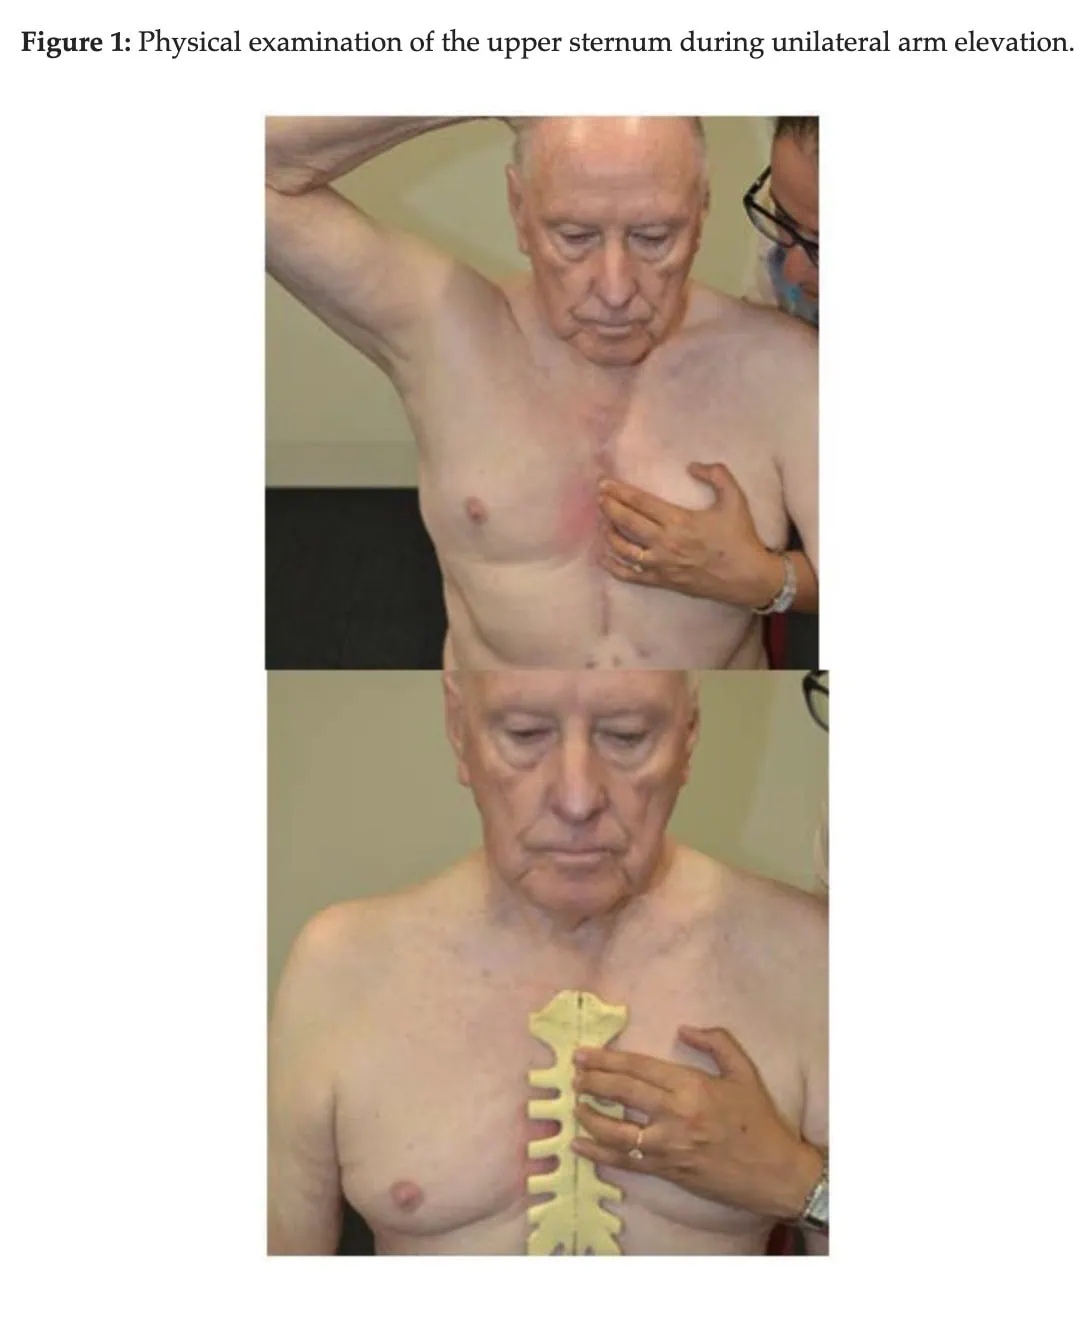

主要结果是使用超声波测量胸骨分离度。 对两半胸骨之间的距离进行量化,并标记出最大分离点。 作为次要结果,胸骨不稳定性量表用于评估从0级(胸骨临床稳定)到3级(胸骨大幅移动或分离)的胸骨完整性。 测量在基线(术后第 7 天)和第 4 周进行。

- 坐姿单侧手臂抬高: 患者举起右臂至与肩同高,然后放松,并重复左臂的动作。 这需要在收缩腹部肌肉的同时进行。

- 站立时单侧手臂抬高: 与上一个练习相同,但要在站立时进行。

- 有阻力的坐姿单侧手臂抬高: 患者举起负重 0.5 千克的右臂至与肩同高,然后用左臂重复该练习。

- 站立式单侧手臂抬高,有阻力: 该练习与上述练习相同,但站立时进行

次要结果支持主要分析,但置信区间更宽。 因此,胸骨不稳定性量表的结果具有更大的不确定性。 一些参与者有了明显改善,而另一些则改善甚微。 不过,胸骨不稳定性量表是一种主观测量方法,因为它是在体格检查时评估胸骨的移动程度。 然而,这需要专业知识,而且要评估的运动量非常小,极易出现误差和研究人员的偏差。 这也许可以部分解释为什么这些研究结果的置信区间要大得多。 El-Ansary 等人(2000 年)报告称,经过培训和标准化检查程序后,评分者之间(99%)和评分者内部(98%)的可靠性达到了完美水平。 不过,这项研究的主观性以及对这种细微动作的触诊可能需要进一步验证。